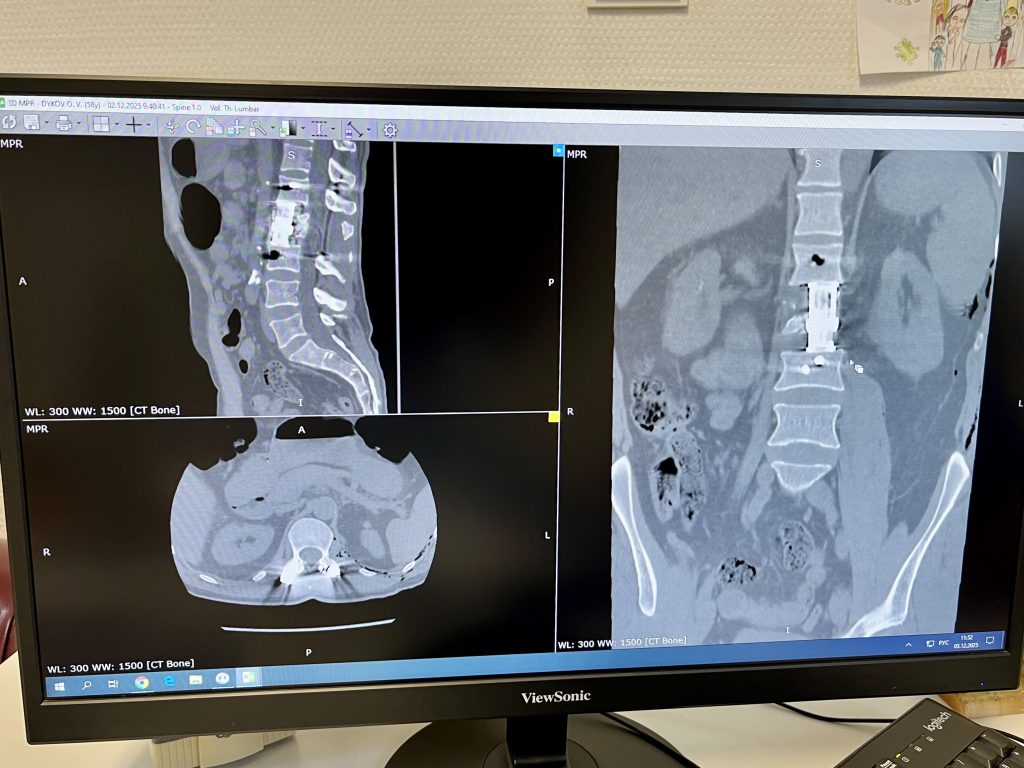

На скорой Олега доставили в больницу Нальчика и экстренно провели операцию, установив 4 винта в поясничный отдел позвоночника.

«Когда пациент поступил на лечение в Федеральный центр нейрохирургии, ему был диагностирован оскольчатый перелом второго поясничного позвонка. Через специальный доступ мы установили мужчине межтеловой кейдж, имплант, замещающий тело позвонка. Операция сложная, не каждый хирург её проведёт, к тому же в центре есть современное оборудование. После успешной операции мужчина поднялся на следующий день и мы его выписали домой. Со временем ему можно будет вернуться к полётам», — пояснил лечащий врач Давид Набиев, заведующий НХО 3 (спинальным) ФЦН Тюмени, к.м.н.